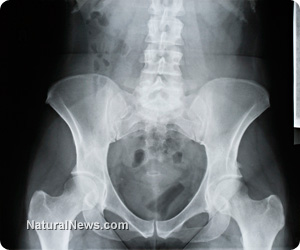

Two journal-published studies, one from China in 2004 and the other from the USA in 2007, reported that cadmium exposure effected measured reductions in bone density, osteoporosis, increased fractures in areas where cadmium pollution is high, and renal (kidney) dysfunction.

The USA study noted that apoptosis (the normal death of a cell to allow new cell generation) was induced prematurely by cadmium, which disrupts the normal life/death cellular cycle, causing an imbalance of bone formation and leading to a cascade of signals that bring about bone disease.